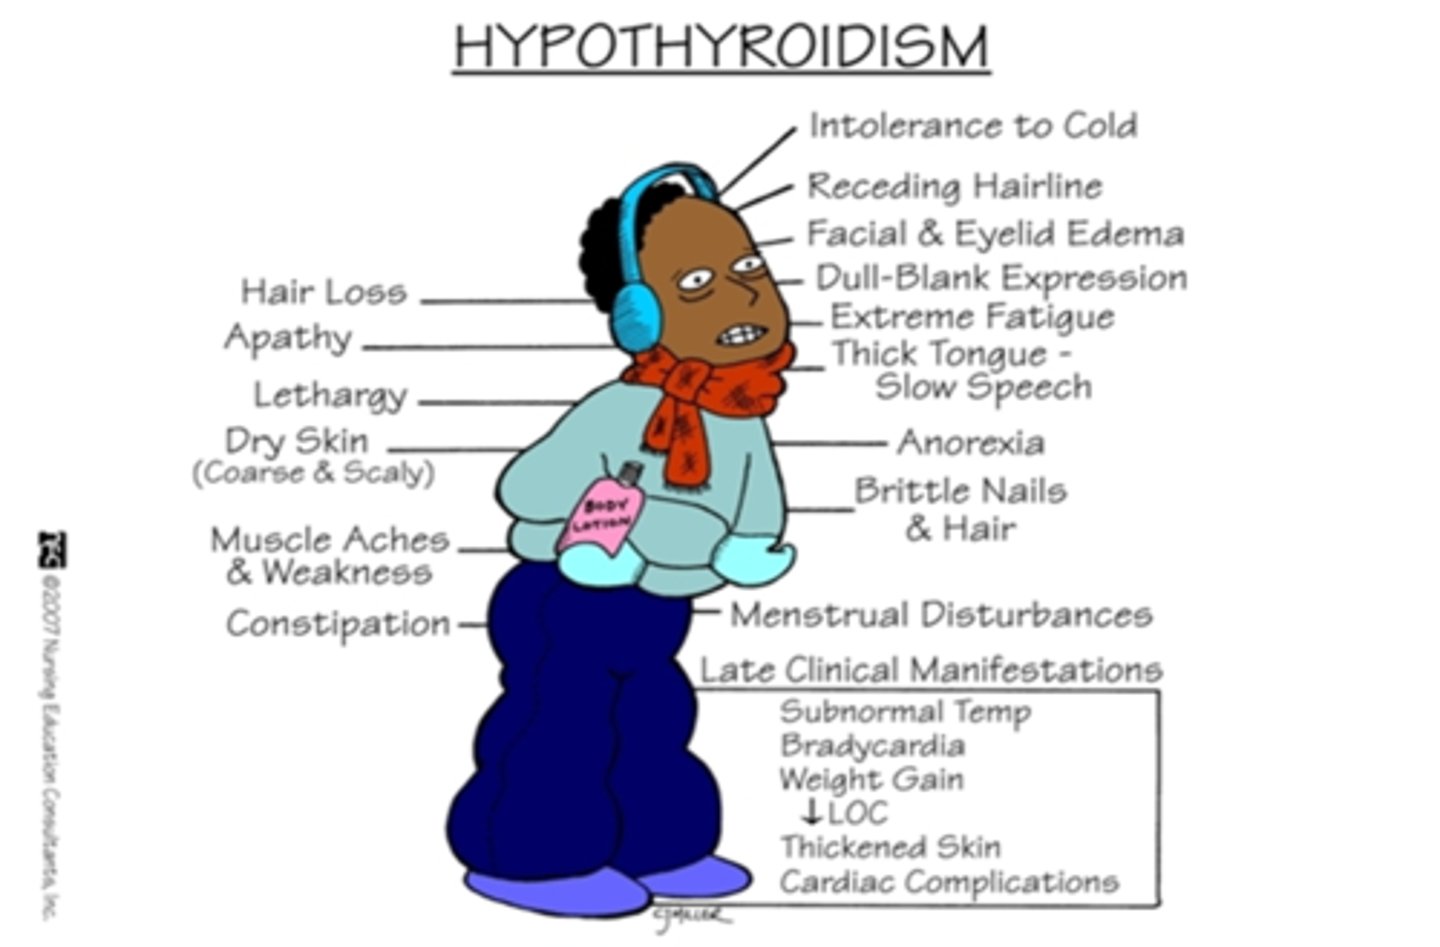

weight gain, dry hair, lower voice, feels cold

hypothyroidism